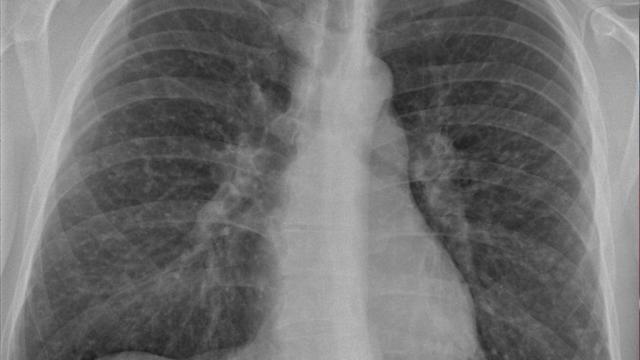

Le diagnostic de sarcoidose est fondé sur les antécédents médicaux du sujet, l'examen physique, des tests de laboratoires, l'exploration fonctionnelle respiratoire et la radiographie thoracique, la tomodensitométrie et l'examen des yeux.